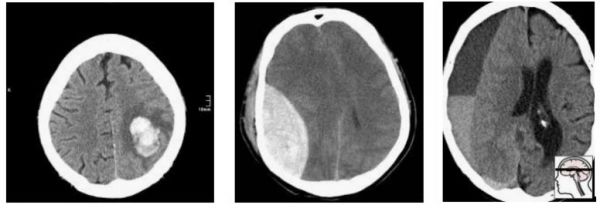

现在,我们对这群人取样,构建我们的测试集:

随机的,最终我们得到了轴外(在大脑外部)出血。在这个测试集上表现良好的模型不一定在实际病患那里表现良好。事实上,我们可以预计,在轴外出血上表现很好的模型以脑内出血为代价而获胜。